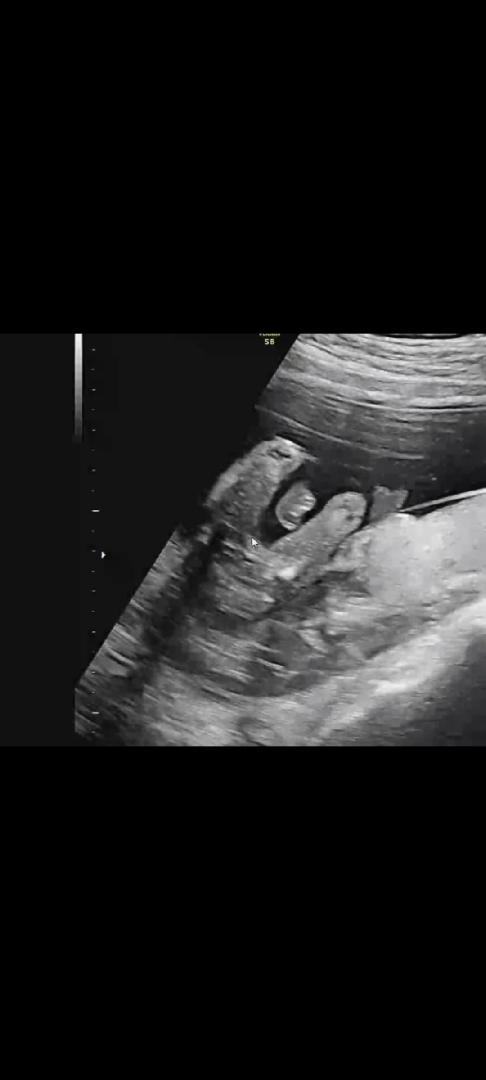

16주차 초음파 딸맞을까용?

의사쌤이 딸인거 같은데 잘안보여서 다음번에 다시보자 하셨어요ㅠㅠ 딸맞는지 봐주세용~

딸같아요 ㅎㅎ 딸들이 잘안보여준데요 ㅎㅎ

16주고 이정도로 매끈하면 딸 맞는것 같아요!